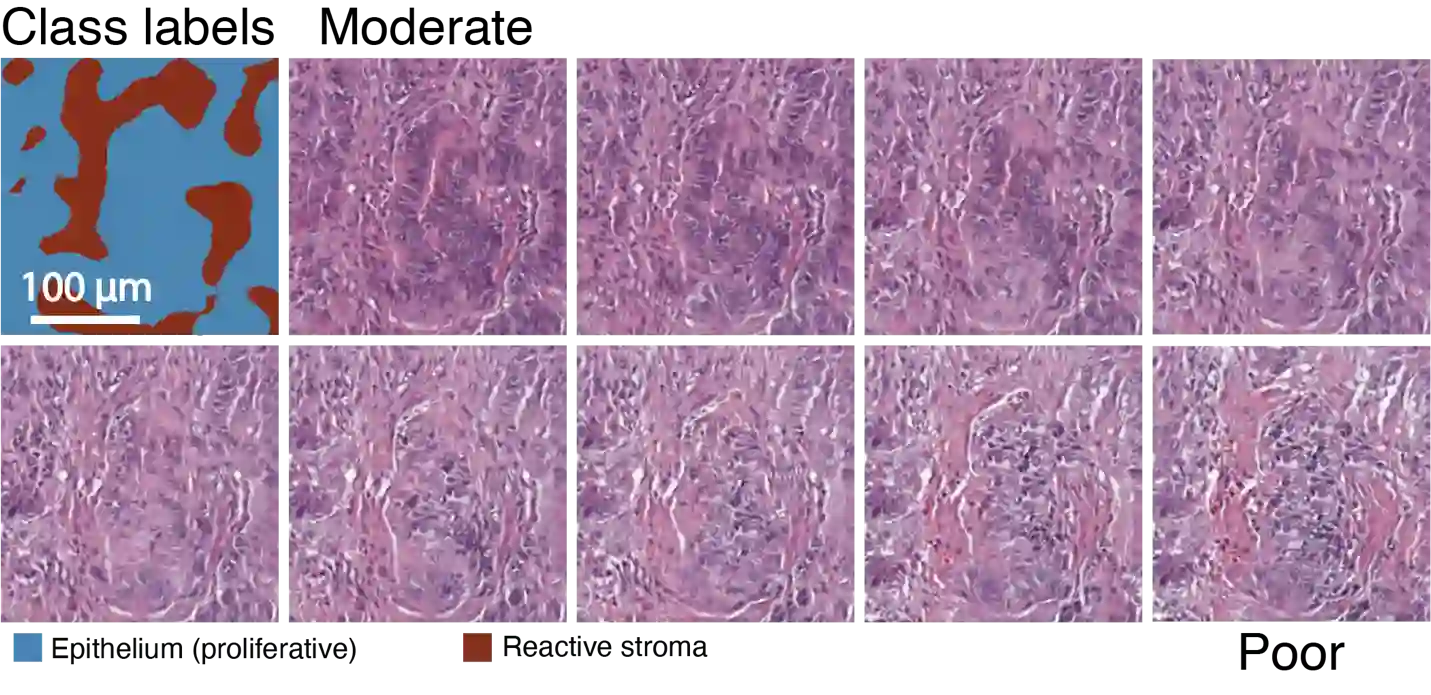

An optical microscopic examination of thinly cut stained tissue on glass slides prepared from a FFPE tissue blocks is the gold standard for tissue diagnostics. In addition, the diagnostic abilities and expertise of any pathologist is dependent on their direct experience with common as well as rarer variant morphologies. Recently, deep learning approaches have been used to successfully show a high level of accuracy for such tasks. However, obtaining expert-level annotated images is an expensive and time-consuming task and artificially synthesized histological images can prove greatly beneficial. Here, we present an approach to not only generate histological images that reproduce the diagnostic morphologic features of common disease but also provide a user ability to generate new and rare morphologies. Our approach involves developing a generative adversarial network model that synthesizes pathology images constrained by class labels. We investigated the ability of this framework in synthesizing realistic prostate and colon tissue images and assessed the utility of these images in augmenting diagnostic ability of machine learning methods as well as their usability by a panel of experienced anatomic pathologists. Synthetic data generated by our framework performed similar to real data in training a deep learning model for diagnosis. Pathologists were not able to distinguish between real and synthetic images and showed a similar level of inter-observer agreement for prostate cancer grading. We extended the approach to significantly more complex images from colon biopsies and showed that the complex microenvironment in such tissues can also be reproduced. Finally, we present the ability for a user to generate deepfake histological images via a simple markup of sematic labels.